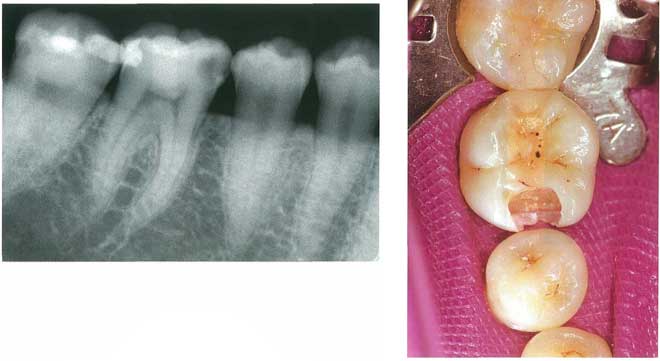

28歳の男性。下顎右側第一大臼歯の疼痛を主訴として来院した。3年前に治療を受けたが,数日前から30分ほどの自発痛が間欠的に起こるという。電気診で閾値が低下している。初診時の口腔内写真とエックス線写真とを別に示す。

スクリーンショット 2017 01 19 16 04 58スクリーンショット 2017 01 19 16 05 03

A グラスアイオノマーセメントで裏層し,コンポジットレジン修復

B 水酸化カルシウムで間接覆髄し,コンポジットレジン修復

C 酸化亜鉛ユージノールセメントで間接覆髄し,コンポジットレジン修復

D 水酸化カルシウムで直接覆髄し,コンポジットレジン修復

E 酸化亜鉛ユージノールセメントで仮封し,経過観察

正答 E

問題文に「間欠的な自発痛」とあるので、CR修復など最終修復に進んではいけません。もし「自発痛」が「冷水痛」であればそれが正答になりえますが、今回の場合は、歯髄の炎症が大きいので、「歯髄鎮静療法」を選ぶ必要があります。鎮静療法につかえるお薬は、ユージノールとフェノール系の2種でしたね。ユージノールは歯髄炎が広まりかけている組織を殴って!黙らせるようなお薬です(アグレッシブ!)。それで歯髄炎が収まれば、歯髄保存しCR充填できますし、自発痛が止まらなければ全部性の歯髄炎に移行したと判断され、抜髄となります。

今回はとりあえず、ユージノールということでCかEが残ろいますが、Cのユージノール+CRは「重合阻害」を起こすのでアウトです!よって、正答はEとなりなす。